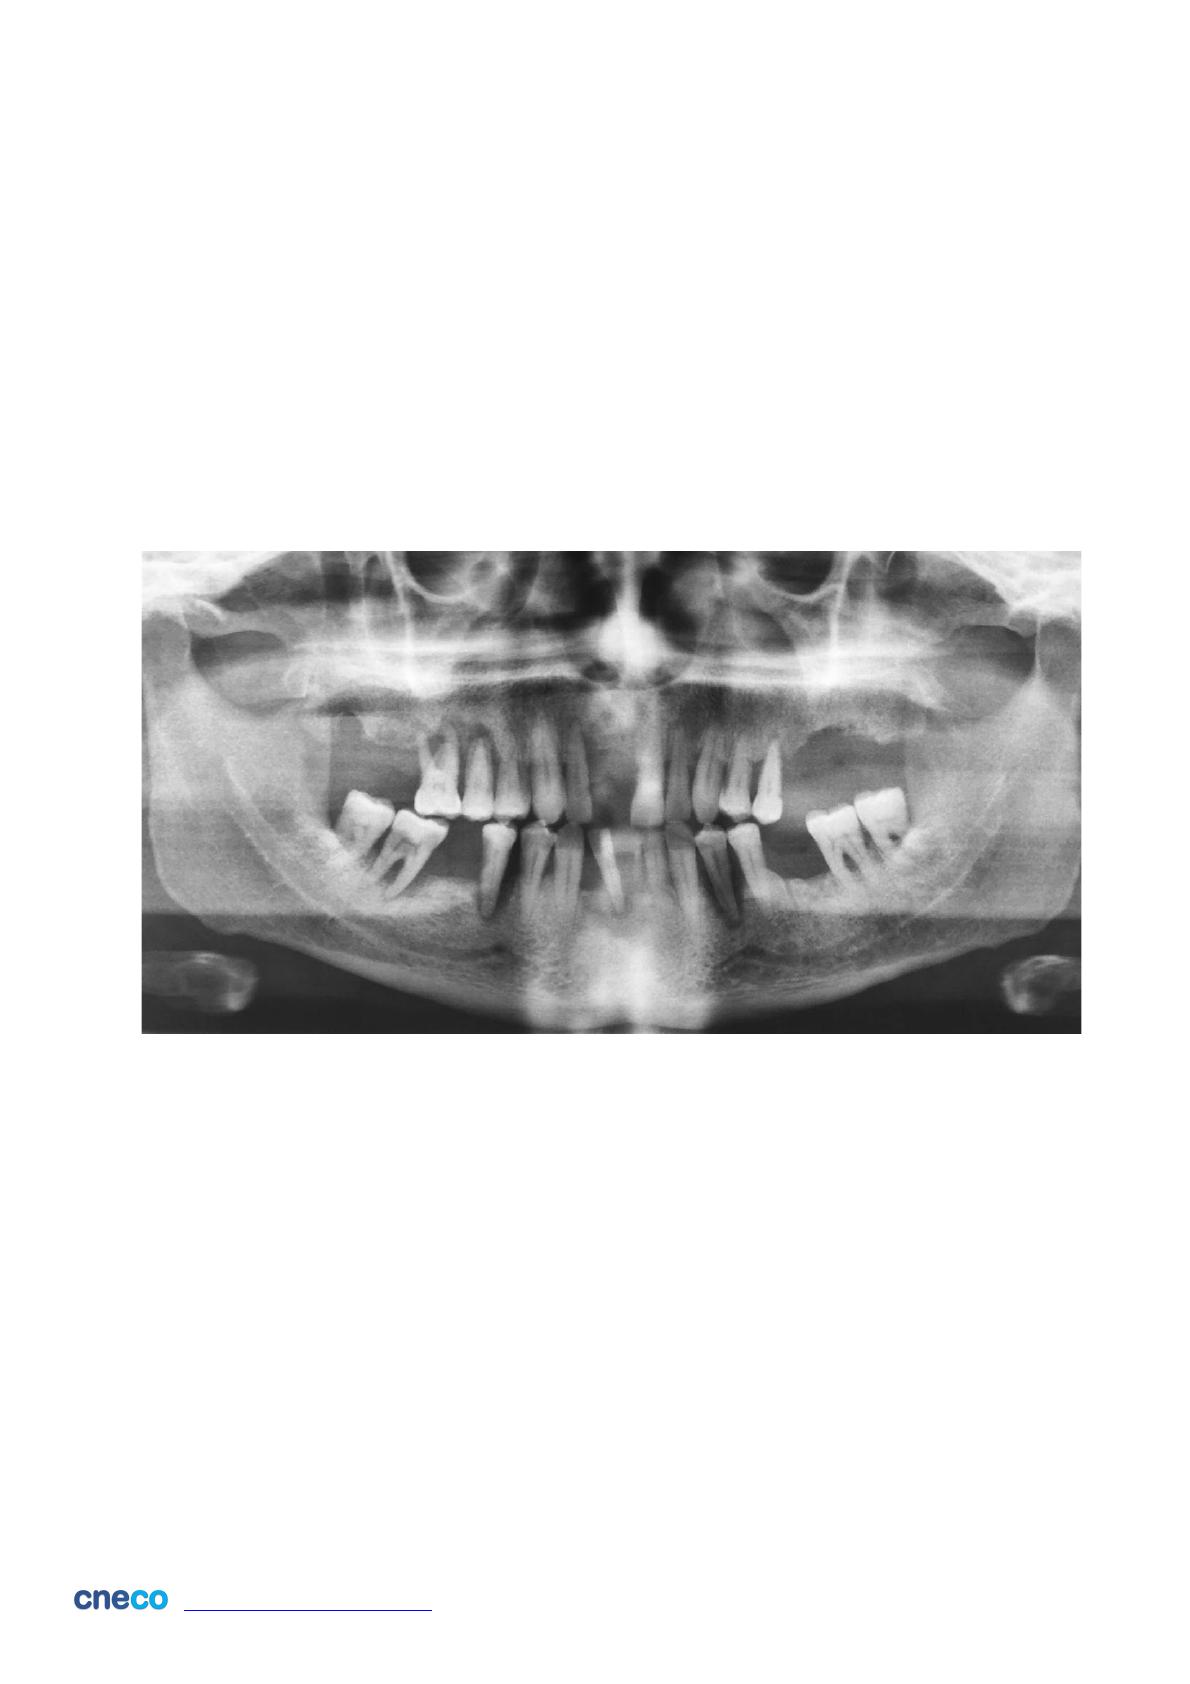

Vous recevez en consultation dans votre cabinet un patient âgé de 66 ans, porteur d’une valve

mitrale prothétique (bioprothèse) depuis une dizaine d’année, adressé par l’un de vos

correspondants omnipraticien. Il est traité par Fluindione (PréviscanÒ 20mg, un demi

comprimé/jour) depuis cette époque. Aucun autre traitement médicamenteux et aucun autre

antécédent médico-chirurgical n’est à noter. Vous réalisez un orthopantomogramme (Figure

ci-dessous).

L’examen clinique exobuccal ne révèle rien de particulier. L’examen clinique endobuccal

révèle la présence généralisée de plaque dentaire et des mobilités de toutes les dents restantes

entre 2 et 3. Ce patient ne bénéficie d’aucune restauration prothétique des édentements

présents.

Diagnostic : Parodontite (1 pt) sévère de stade IV (1 pt) généralisée (1 pt) (selon la

récente classification de l’Académie Américaine de Parodontologie et de la Fédération

Européenne de Parodontologie : référence 1).

Justification : Alvéolyse sévère voire terminale généralisée (1 pt); Mobilités dentaires

généralisées (1 pt).